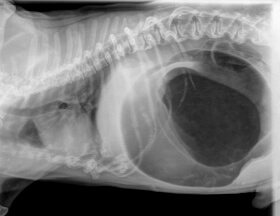

Показания к рентгену желудка

Рентген — метод диагностирования, при котором внутренние органы и скелет животного проецируются на специальную бумагу или пленку. Активно применяется в ветеринарной практике, так как позволяет за короткий период получить детальную информацию о состоянии питомца.

Распространенная причина для выполнения Rg-исследования — возникновение непроходимости в полости желудка. Показательными признаками для выполнения диагностического исследования являются:

Все симптомы, указанные выше, могут сигнализировать о возникновении непроходимости из-за:

• проглатывания инородного тела;

• онкологического заболевания;

• возникновение воспалительного процесса на слизистой (гастрит или образование язвы);

• заворота кишечника.

Как проводится исследование желудка?

Рентген желудка животного возможно сделать в ветеринарной клинике либо в домашних условиях. Во втором случае наш специалист выезжает на адрес по предварительной записи. Процедура выполняется при соблюдении следующих условий:

1. При подозрении на заворот кишок или патологическое расширение полости желудка рентген выполняется строго на правом боку (право-латеральная проекция). Иное положение может привести к негативным последствиям (смерть животного).